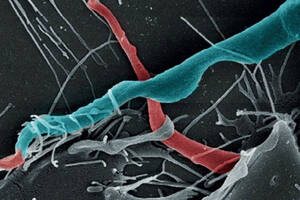

Un parásito discreto

El Trypanosoma cruzi logra que las células funcionen en su beneficio